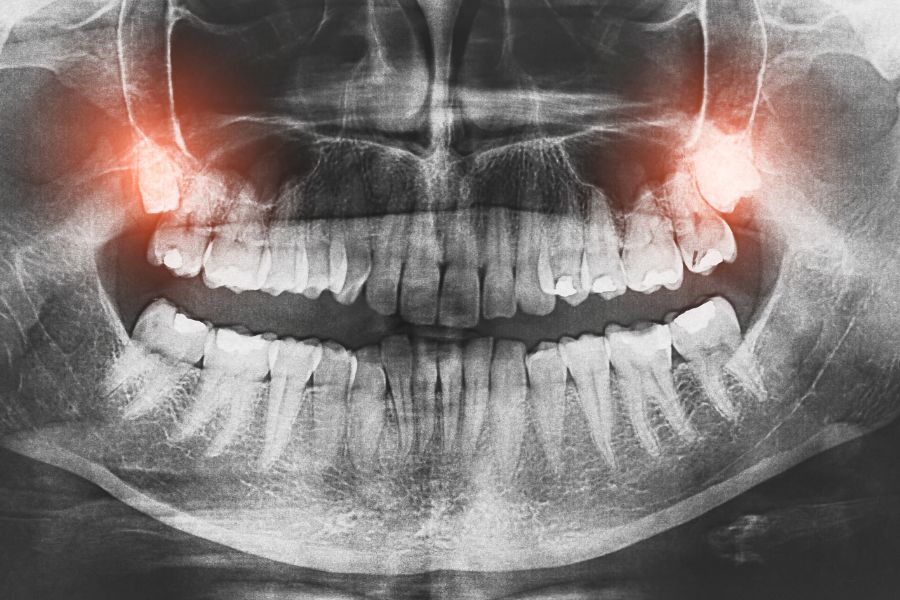

Często konieczne jest wykonanie zdjęć rentgenowskich (np. pantomografii czy cefalometrycznego zdjęcia bocznej projekcji czaszki) oraz pobranie wycisków zębów lub wykonanie cyfrowego skanu jamy ustnej. Na podstawie tych materiałów ortodonta przygotowuje model Twoich zębów i precyzyjnie planuje leczenie.

- Zęby ektopowe – to zaburzenie wyrzynania polegające na tym, że ząb lub jego zawiązek znajduje się w miejscu, gdzie zęby normalnie nie występują. Może to dotyczyć zębów mlecznych, stałych, a także nadliczbowych. Zdarza się, że ząb "wędruje" do jamy nosowej, zatoki szczękowej, a nawet do oczodołu. Przyczyny są różne: od uwarunkowań genetycznych, przez urazy twarzy, po torbiele, guzy czy stany zapalne kości i stłoczenia zębów. Leczenie takich przypadków wymaga cierpliwości i często współpracy ortodonty z chirurgiem szczękowym.